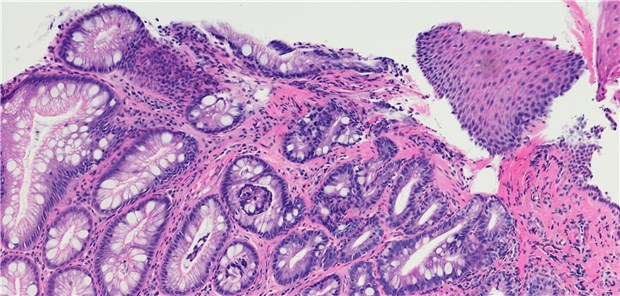

Ustekinumab punktet bei Morbus Crohn